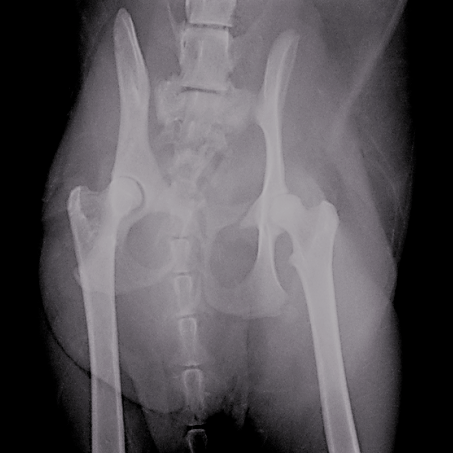

術前撮影 骨盤骨折、大腿骨骨折

術後撮影 プレートにて整復